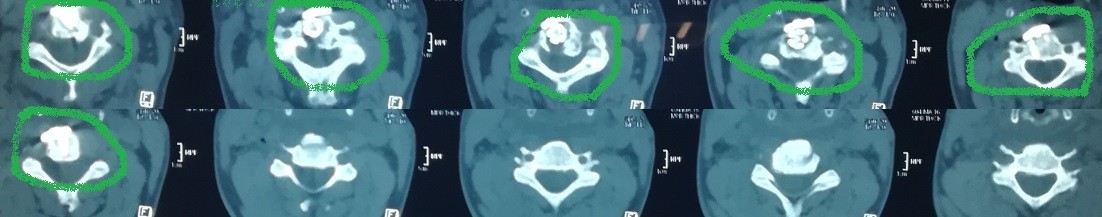

تثبيت امامي لكسر وتاكل بجسم الفقرة الثالثة العنقية

anterior fixation of a fracture and wear of the body of the third cervical vertebra

A successful anterior fixation surgery was performed to treat fracture and erosion in the vertebral body of cervical vertebrae. This specialized procedure aims to restore cervical spine stability and address vertebral damage resulting from injury or inflammation.